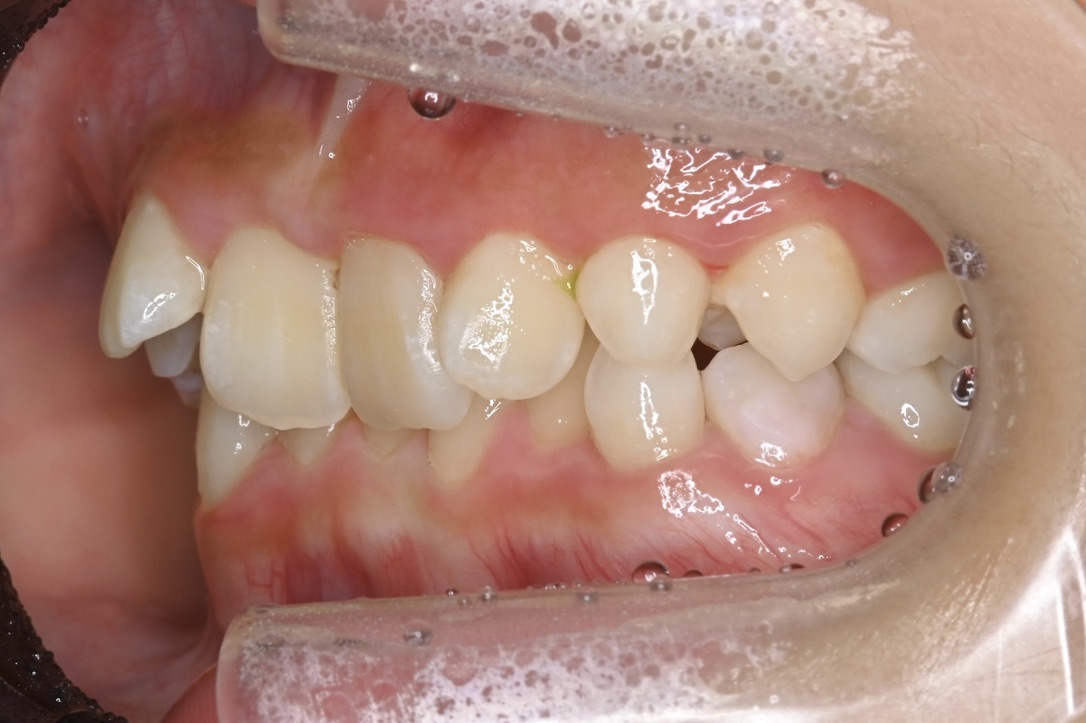

BEFORE

主訴 通っている歯医者で矯正した方がいいと言われて気になっている。下の前歯がでこぼこしている。

診断名・主な症状 下顎前歯の叢生を伴う過蓋咬合

治療内容 上下の歯並びの幅を拡げつつ、前歯の関係を改善しました。

使用装置 急速拡大装置

リンガルアーチ

機能的矯正装置(マイオブレース)

抜歯部位 抜歯なし

治療期間 2年 + 後戻り止め期間(3年 )

通院回数 20回

費用 50万円程度(税別)  29331